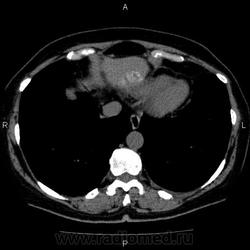

- https://radiomed.ru/sites/default/files/styles/case_slider_image/public/user/5278/10003_0.jpg?itok=VKMojSj8

Это кальцификация. Бывшая гематома, бывший воспалительный процесс, паразитарное поражение, гемангиома, сосудистая мальформация, злокачественное нечто либо метастаз. Без клиники, пола, возраста и болюсного КТ... ну допустим, я поставлю на солитарный метастаз. И это 50/50, т.е. либо я права, либо нет.

гидативную нежизнеспособную кисту. Гемангиома гиподенсна относительно здоровой паренхимы, да и гематома так выглядеть не может.

На эхинококковую кисту похожа

Похоже на кальцинированную эхинококковую кисту печени; для уточнения КТ с болюсным мультифазным контрастированием; консультации гастроэнтеролога и онколога.

"Образование" 3 года без динамики. На УЗИ написали гемангиому. Спасибо всем.